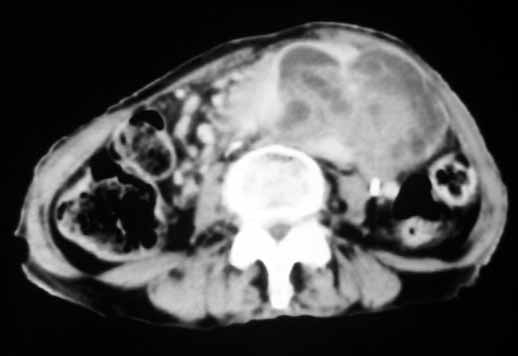

以下是引用天南地北在2007-4-30 17:42:00的发言:[br]增强扫描显示腹主动脉给包绕、推移。肿块不规则强化,[br]修正我在平扫的诊断[br]支持考虑:间叶源性肿瘤可能性大

以下是引用余辉在2007-4-30 18:01:00的发言:[br]病灶前方的条状增强影是什么?若是胰腺,位置似乎有点低,若是十二指肠,似乎又不诫该是那样强化,姑且将其看作胰腺吧,那么考虑来源于胰腺粘液囊腺瘤可能性大,其次考虑来源于肠系膜或者后腹膜的肿瘤如平滑肌肉瘤,异位嗜铬细胞瘤及淋巴瘤等。

以下是引用zyx168在2007-4-30 23:24:00的发言:[br]考虑:间叶源性肿瘤可能性大